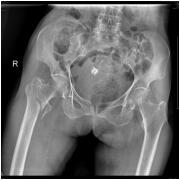

我院骨科繼2016年5月16日成功地為一名平海鎮(zhèn)平海村101歲老人施行右髖部骨科手術(shù)后……